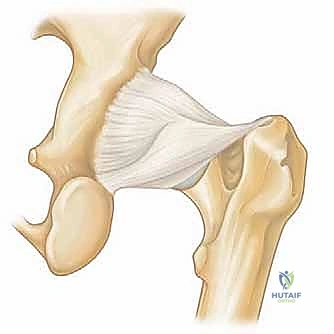

يُغطى كل من الكرة والتجويف بطبقة ناعمة من الغضروف المفصلي الذي يسمح للعظام بالانزلاق بسلاسة فوق بعضها البعض. كما يحيط بحافة التجويف حلقة من الغضروف الليفي القوي تُسمى الشفا الغضروفي (Labrum). يعمل الشفا كختم مطاطي يحافظ على السائل الزلالي داخل المفصل ويزيد من استقراره.

2. تمزق الشفا الغضروفي (Labral Tears)

الشفا الغضروفي هو الحلقة التي تحافظ على استقرار المفصل. يمكن أن يتمزق بسبب الإصابات الرياضية (مثل الجمباز، كرة القدم، أو الفنون القتالية) أو بسبب حالة الاصطدام الفخذي الحقي. بالمنظار، يتم خياطة هذا التمزق وتثبيته بخطاطيف دقيقة جداً (Suture Anchors).